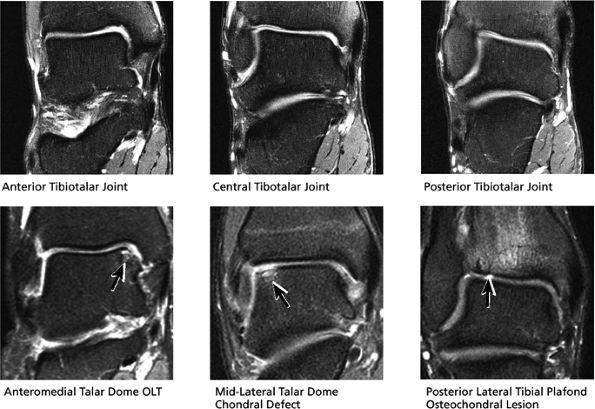

FIGURE 5.40 Tibiotalar Joint.

|